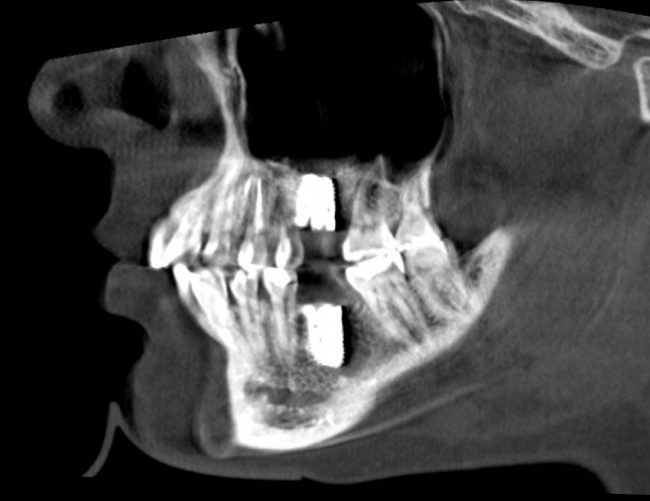

Для этого мы сделали КЛКТ:

И КЛКТ показала нам, что с имплантатами и окружающей костью всё зашибись. Через 12 лет после операции, отсутствия наблюдения, пофигизма в замене временных коронок! Нужны ли тебе еще какие-нибудь доводы в пользу долгосрочной эффективности метода?